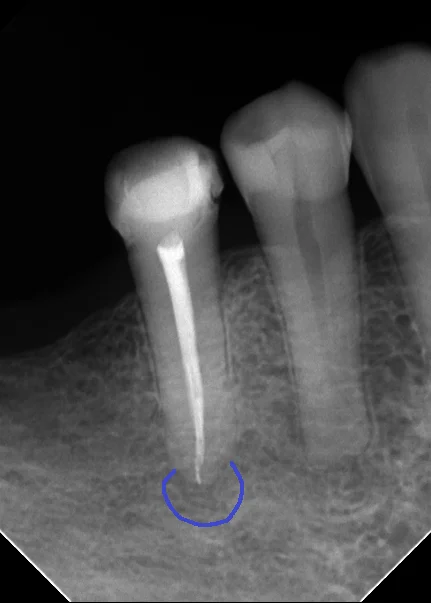

そして3回くらいの治療の後、根の中の状態としては問題が無くなったため、お薬を詰めました。

無事に折れたファイルを除去することができ、根の先まで綺麗に到達することが出来ました。

こちらの記事でも書きましたが、根の先の溶けた骨は数年単位でじりじりと膿に溶かされて行っていますので、そんな直ぐに骨が出来てこないという事も良くあります。

今回はトータルで2ヶ月掛かっていますが、根管充填時点では根の先の骨に明らかな治癒傾向は認められませんでした。

それがこちらです。

根の先には骨がしっかりと出来てくれています。(青い丸の部分)

膿があった影も完全に消失することが出来ましたね。

また入れていたセラミックの適合も非常に良好です。(紫の丸の部分)

段差も一切なく、非常に適合良く入っているのが分かるかと思います。